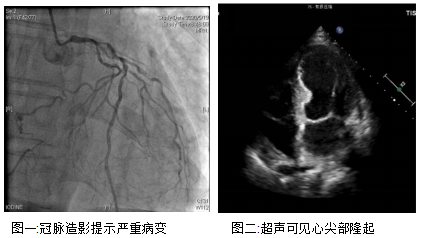

老孙就是同时被冠心病和室壁瘤困扰的患者。3年前他便出现了胸闷、憋气的症状,半年前症状加重了,在清华⻓庚医院做了造影,证实是严重的左主干+三支病变,必须做冠脉搭桥才有望改善心脏缺血的现状。但老孙的心功能却不容乐观,射血分数只有30%,仅仅相当于正常人的一半,而且超声还可以看到老孙的心尖部变得薄而圆钝,心脏跳动时几乎不运动,提示他还有室壁瘤形成。